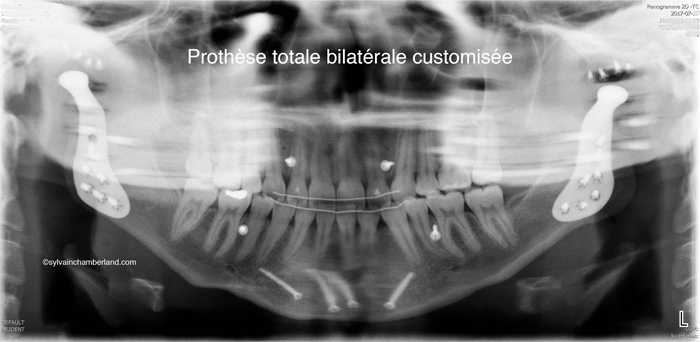

5- La radiographie de droite représente l’état des condyles complètement résorbés du cas clinique illustré sur la photo de gauche.

Ce patient a reçu des prothèses totales des 2 articulations temporomandibulaires.

Une résorption condylienne bilatérale cause une rétrusion progressive de la mandibule, une réduction de la hauteur de la branche montante (microrami) et une diminution de la largeur de oropharynx augmentant le risque d’apnée du sommeil.

Sur la radiographie de gauche, la plus grande barre horizontale représente la 2e vertèbre cervicale. Normalement, l’angle goniaque est situé à cette hauteur. La résorption des condyles a causé un raccourcissement de la branche montante de sorte que l’angle goniaque se trouve à hauteur de la 1re vertèbre cervicale. La petite barre horizontale indique la largeur du tractus oropharyngé. il faut avoir normalement 10 à 15 mm. Dans ce cas, il y a à peine 5 mm de largeur.

Le cas avec résorption a nécessité le remplacement des articulations par des prothèses totales customisées.

Prothèse totale bilatérale customisée des ATMs